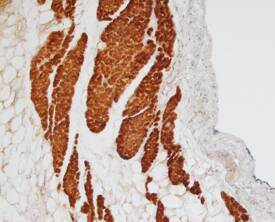

MyBPC3 antibody in Human Heart by Immunohistochemistry (IHC-P).

MyBPC3 in Human Heart.

MyBPC3 was detected in immersion fixed paraffin-embedded sections of human heart using Sheep Anti-Human MyBPC3 Antigen Affinity-purified Polyclonal Antibody (Catalog # AF7439) at 15 µg/mL overnight at 4 °C. Tissue was stained using the Anti-Sheep HRP-DAB Cell & Tissue Staining Kit (brown; Catalog # CTS019) and counterstained with hematoxylin (blue). Specific staining was localized to cytoplasm of muscle cells. View our protocol for Chromogenic IHC Staining of Paraffin-embedded Tissue Sections.